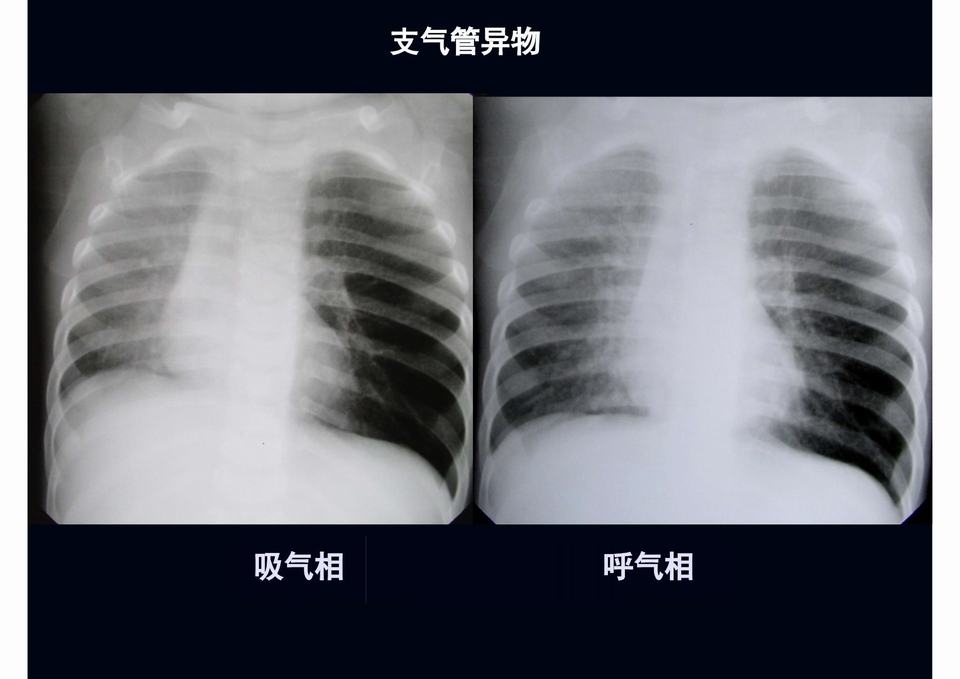

【PPT】儿童胸部影像学